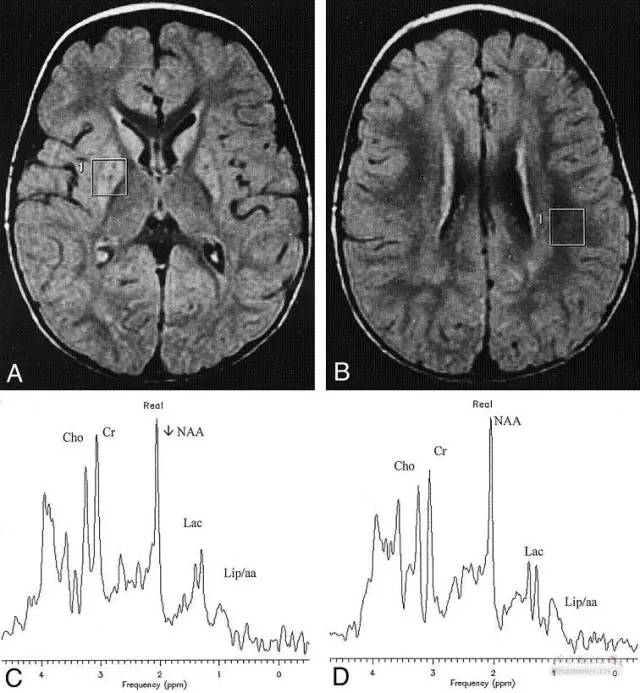

自身免疫性脑炎

图片尺寸895x1174